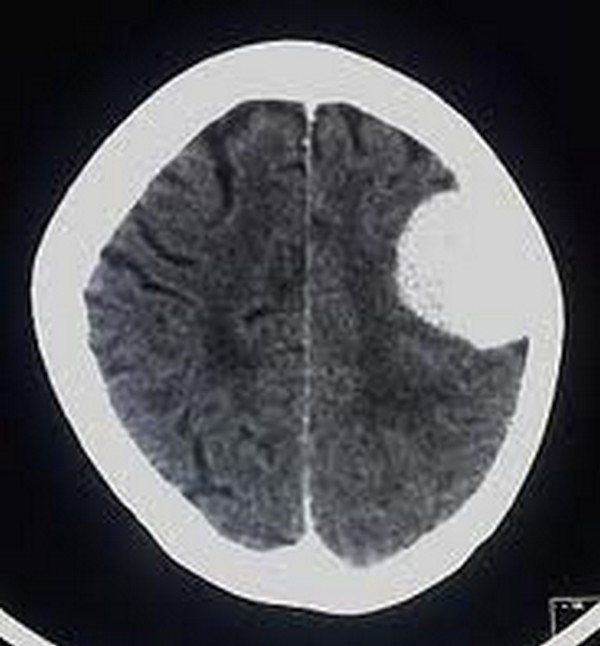

BRAIN TUMOR IN TEMPORAL LOBE Dental X Rays Cause Brain Tumors Ionizing radiation is a consistently identified and potentially modifiable risk factor for meningioma, the most frequently reported primary. Dental X Rays Cause Brain Tumors.